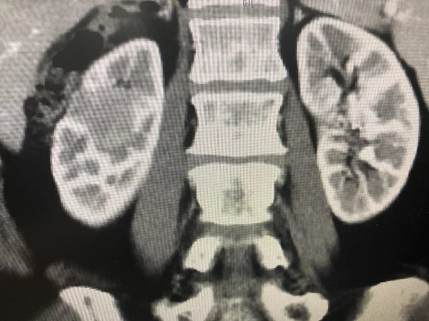

病例六,69岁女性,发现双肾占位10年。10年前于外院发现双肾占位,考虑错构瘤,右肾肿物4cm,定期观察。2周前复查CTU增强提示双肾多发错构瘤,大者位于右肾下极,7.3cm×3.9cm×6.7cm,左侧大者约4.3cm×4.3cm。行机器人辅助腹腔镜双肾部分切除术,术者:张树栋教授、郝一昌教授。术中右肾肿瘤位于肾脏下极,且与肾门关系紧密,仔细分离需小心输尿管损伤。